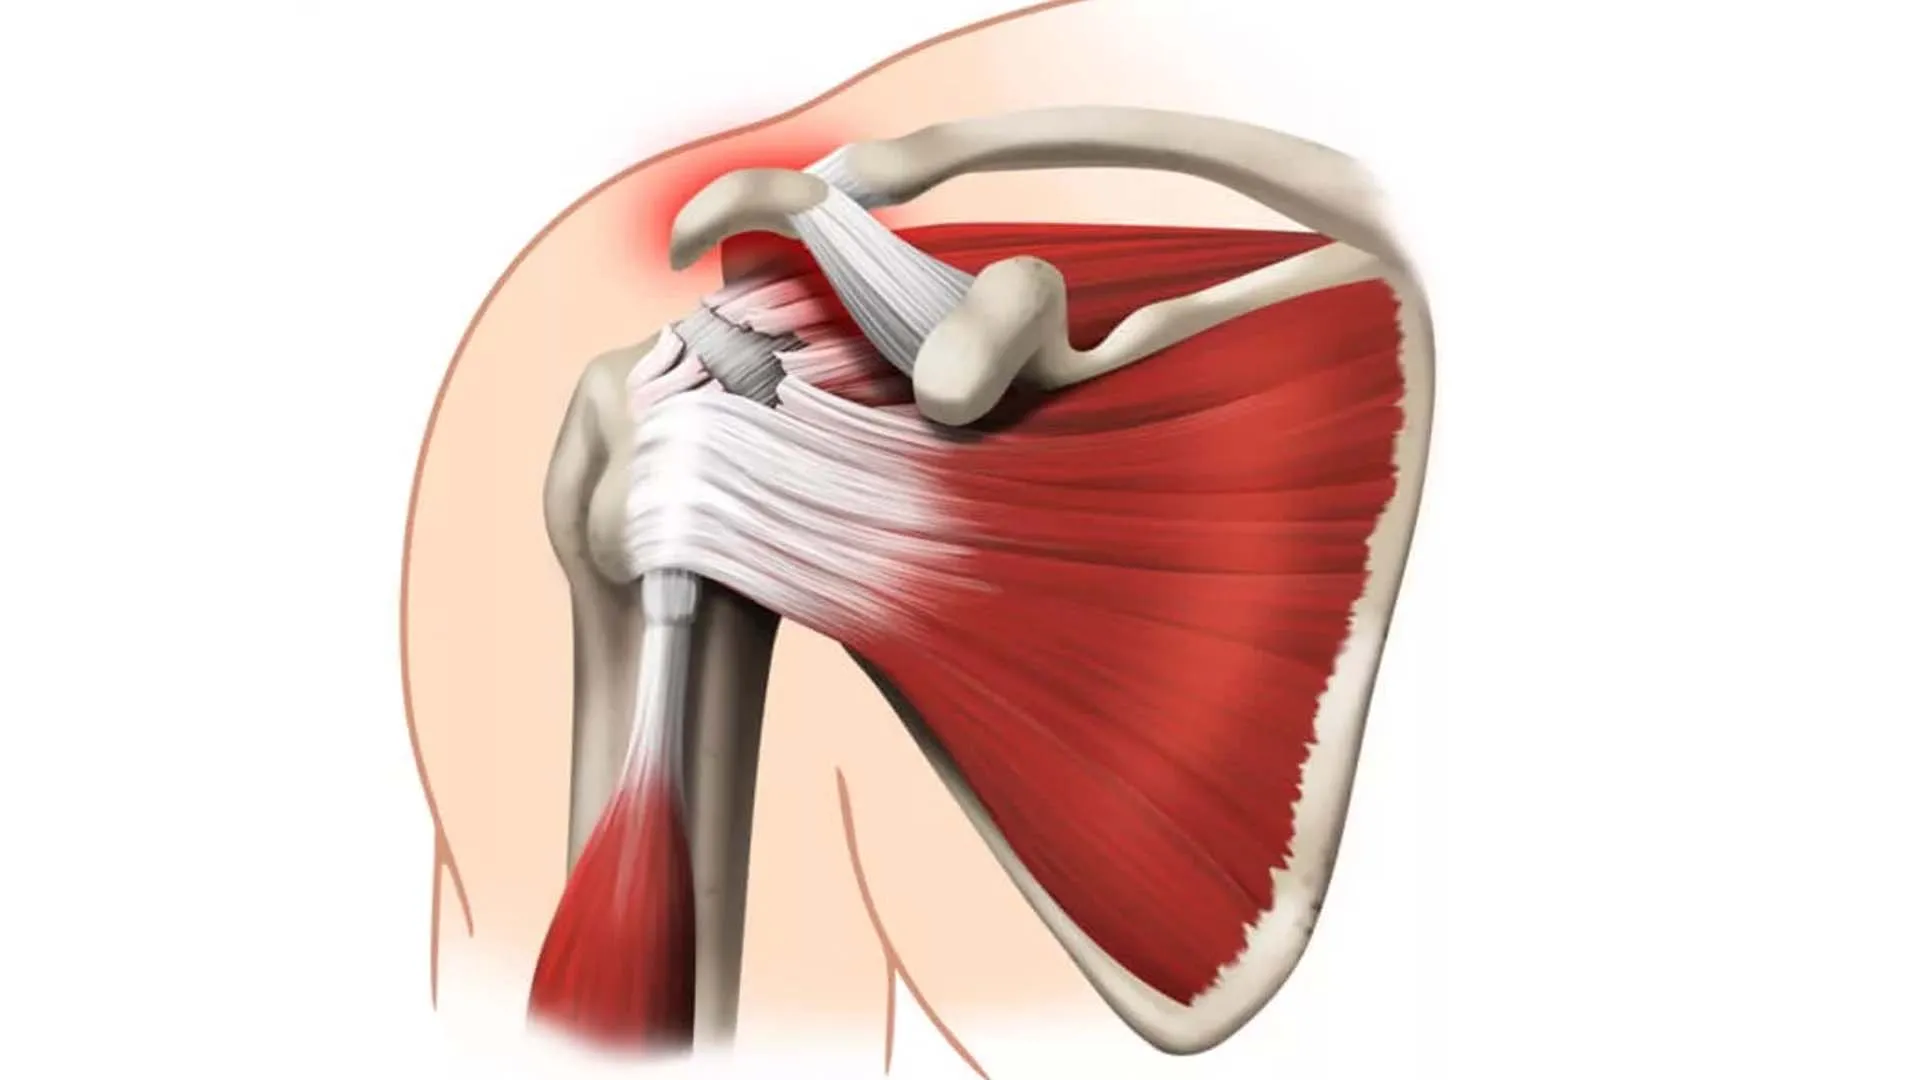

Фотографии поддельтовидной мышцы плечевого сустава